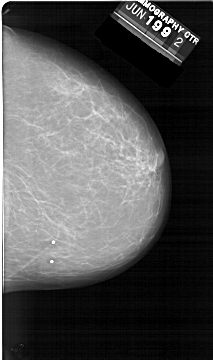

A_1398_1.RIGHT_CC

RIGHT_CC LINES 6466 PIXELS_PER_LINE 3826 BITS_PER_PIXEL 12 RESOLUTION 43.5 NON_OVERLAY